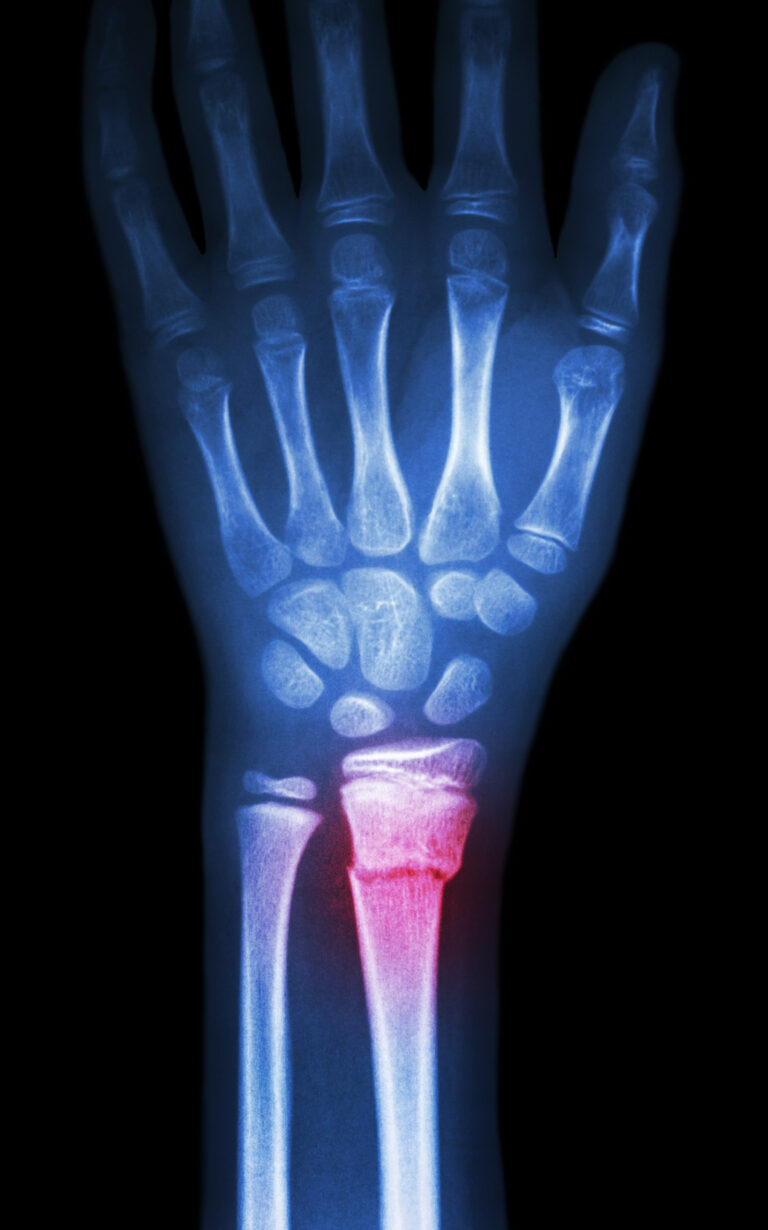

WHAT IS WRIST ARTHRITIS- DISTAL RADIAL FRACTURES?

Also referred to as Colles’ or Smith’s fracture, Wrist Arhtritis – Distal Radial Fracture is often associated with the shortening of the radius. If the fracture occurs close to the wrist, this can alter the alignment of the joint, causing pain and loss of function.

Suggest X-ray

Choosing the right hand therapist starts with them being able to read your X-rays and then fabricate the right brace for you. The therapists at Action Rehab Hand Therapy Clinic are experienced in assessing and reading X-rays.